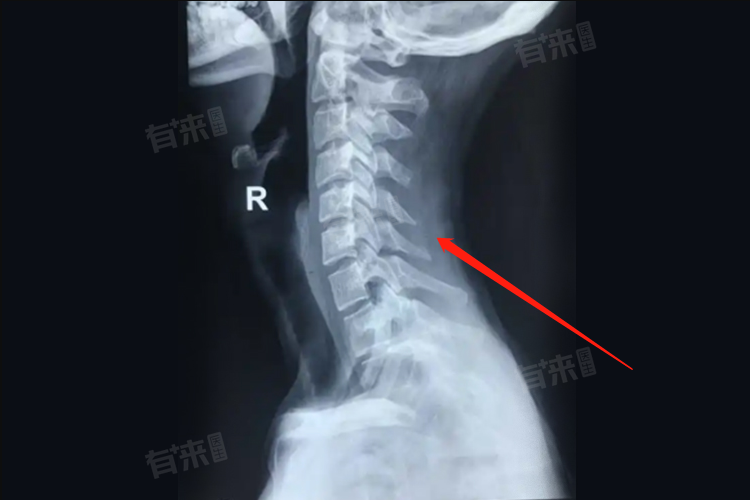

颈椎强直是一种常见的颈部疾病,由于颈椎退行性病变或长期劳损导致颈椎曲度消失、颈椎强直,形成颈椎病,患者常常感到颈部僵硬、疼痛,甚至影响到日常生活,可以选择药物、物理等方法进行治疗。